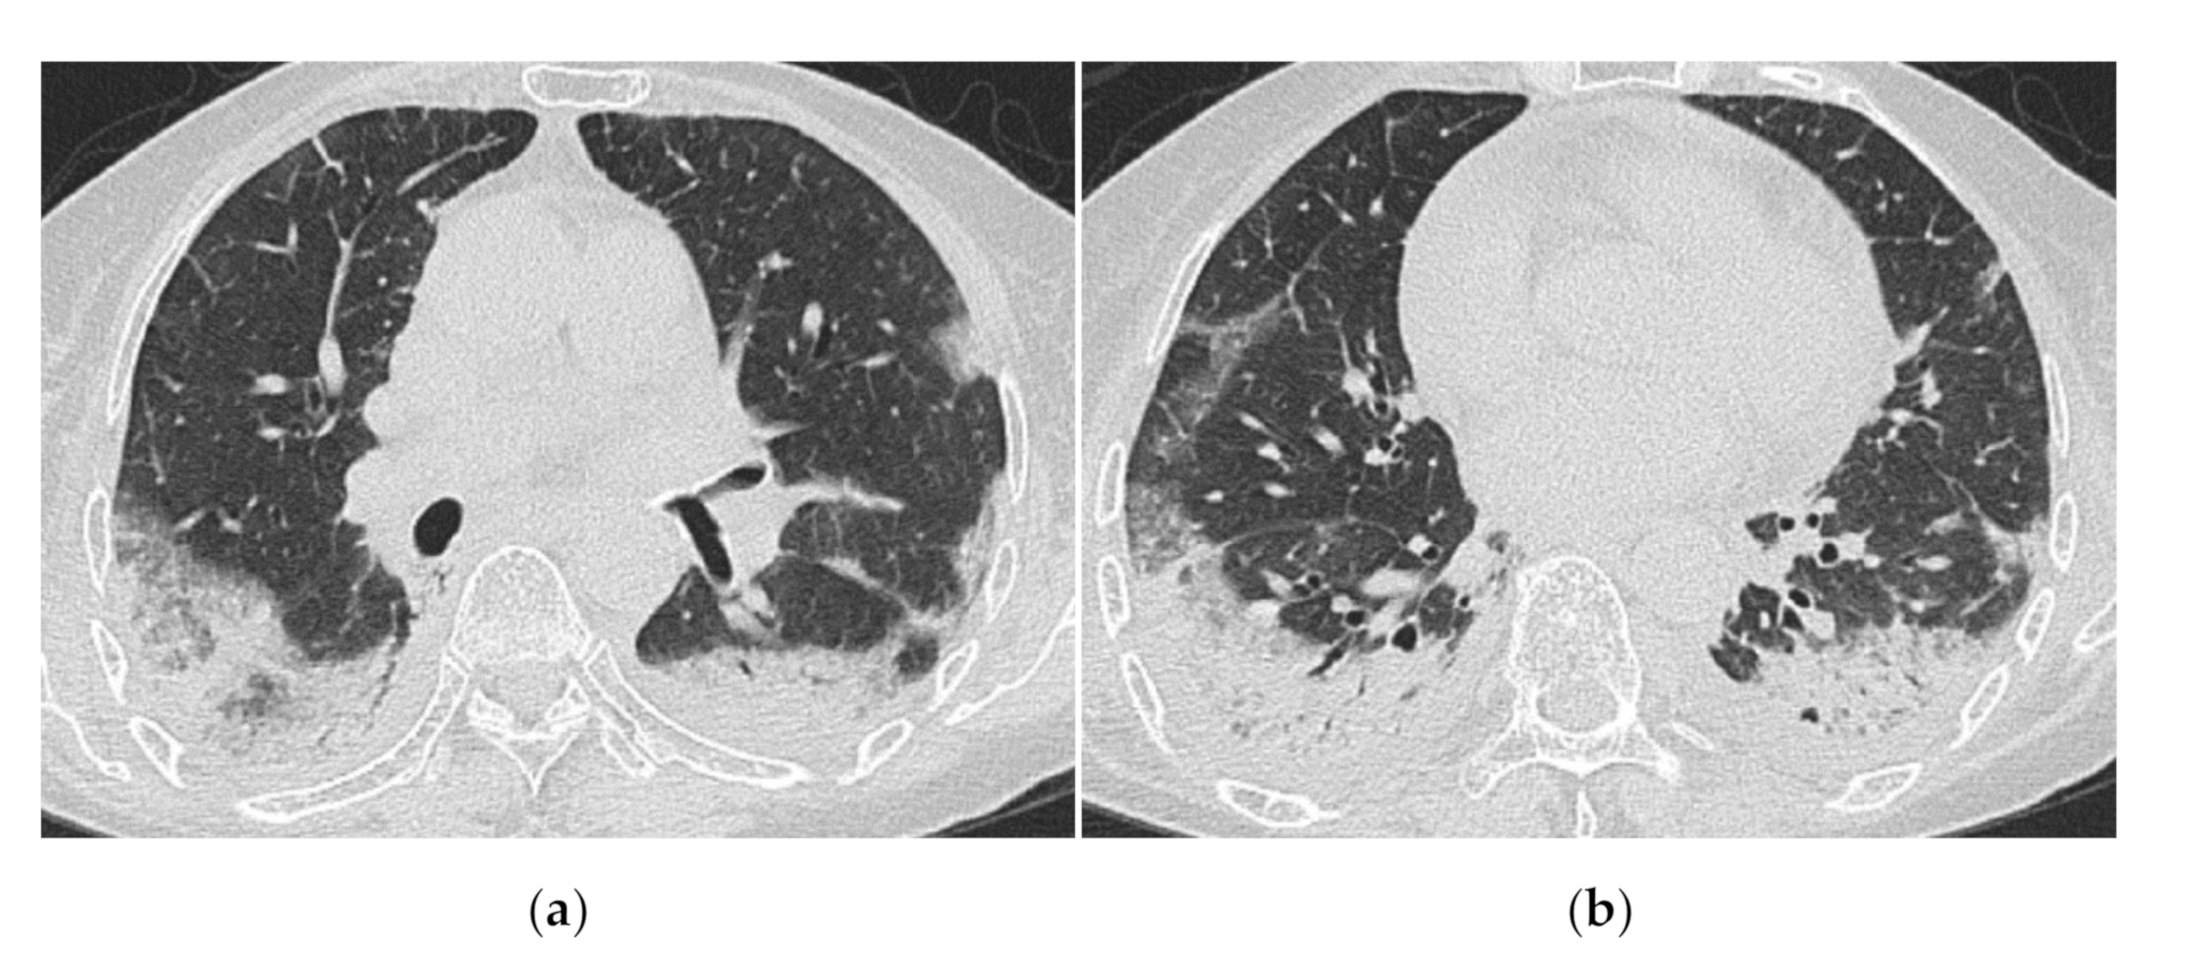

3.2. Anti-MDA5 Antibody (Anti-MDA5 Ab)

HRCT Findings of Patients with Anti-MDA5 Ab